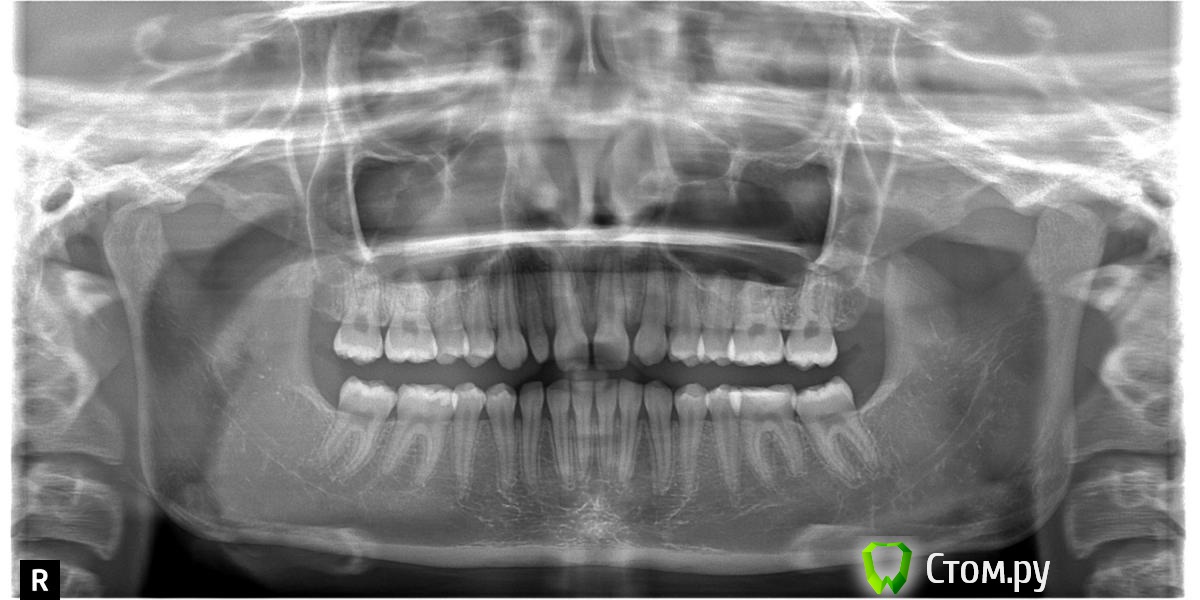

Джоконда Опубликовано 22 сентября, 2014 Автор Поделиться Опубликовано 22 сентября, 2014 (изменено) Добрый день!Итак: У девочки отсутствует зачаток второго зуба на ВЧ, а другой второй зуб шиповидный. Бруксизм появился как стали расти постоянные зубки. Из-за отсутствия второго зубика было принято решение сдвигать зубки вперед. Прошли ортодонтическое лечение с помощью брекет системы 20 месяцев. Зубки расставлены, и между ними есть промежутки, хотя изначально промежутков между первыми зубами не было. Сейчас девочка на ночь одевает капы и только на нижнюю челюсть, верхние стали сходиться. В капе появились дырочки. Скрежет зубами продолжается. К нервопатологу мы обратились из -за сильных головных болях, утомляемости, плохого настроения - все это появились год назад. Прошли обсследование и врач нам сказал, что вегето-сосудистая дистания. Выписали уколы и таблетки. Курс лечения прошли. После уколов головные боли прошли, даже появилось настроение делать уроки. Сейчас головных болей практически нет, но скрежет продолжается. Я конечно понимаю, что нужно как-то расслаблять мышцу, витамины, соляная ванна. Но проблема все равно останется. Так же я заметила, что изменилась форма лица, оно стало квадратным. Девочка очень комплексует из-за эстетики и стираемости зубов. Я конечно, понимаю, что все хотят заработать, и я готова платить, но....для меня главное не навредить здоровью ребенка. Я прилагаю ТРТ+ОПТГ. Изменено 22 сентября, 2014 пользователем Джоконда Ссылка на комментарий

Skip Опубликовано 24 сентября, 2014 Поделиться Опубликовано 24 сентября, 2014 Зачем? Примерный срок имплантации - 18 лет, не рантше. Раздвинуть зубы обратно и потом три года пытаться удержать? Нелогично. По плану лечения согласен с А.О. Но года через 3-4. Пару лет, примерно, уйдёт на создание вертикального измерения окклюзии, плюс RHG по всей видимости. Разумеется, что я это на себя примеряю и с функциональной ортопедией челюстей. Учитывая, что школьница, использование аппаратов только дома, а значит сроки лечения растянутся и не успеешь оглянуться, как 18 лет, тем более они все ранние сейчас)) Беспокойство вызывает вот эта картина на ТРГ, где можно заметить прекрасное соотношение челюстей между собой, но вместе с этим нижняя челюсть дистализирована, а это значит, что существует потенциальный риск развития ДВНЧС, плюс вертикальное измерение опять же: http://i6.pixs.ru/storage/6/7/5/99955jpg_4352041_13969675.jpg Ссылка на комментарий